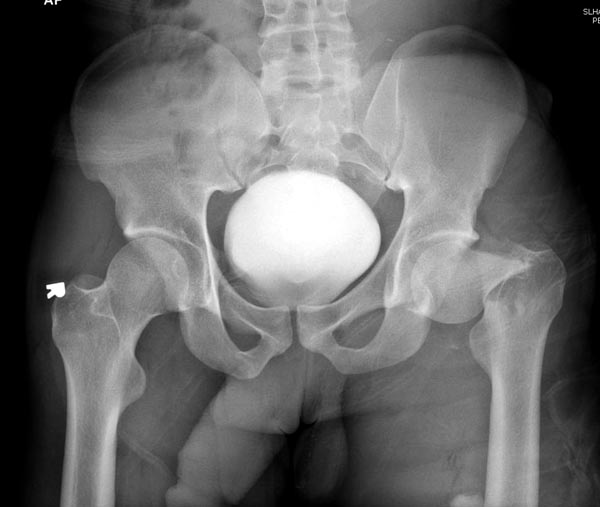

Пока надо делать снимки в классических укладках, т.е. хотя бы в двух проекциях. А по тактике из всех переломов: шейка является приоритетным и ургентным. Идеально фиксировать канюлированными винтами, но усложняется тем, что имеется перелом верхушки вертела. Навряд ли получится закрыто, надо открывать. Все зависит от возможностей на месте (писали насчет DHS), можно и интрамедуллярный гвоздь, но не надо укорачивать, только пустить overlapping, т.е. пластина от DHS покрывает часть гвоздя.

Здесь выставлен ренгенограммы больного, ему 21, травму получил в результате высокоскоростной погони на украденной машине, которая закончилась смертью трех остальных “боевых комрадов”. Начатую коллегой открытую операцию на шейке пришлось закончить мне, установкой винтов и ретроградной фиксацией бедра. Выписка в обычное сроки и наблюдался амбулаторно. Каждый раз напоминали о возможности осложнений ввиде несращения! По истечению 4 месяцев появились признаки варусной деформации. На СТ срезах несращение шейки и бедра. Риминг, замена на более толстый гвоздь и вальгусная остеотомия.